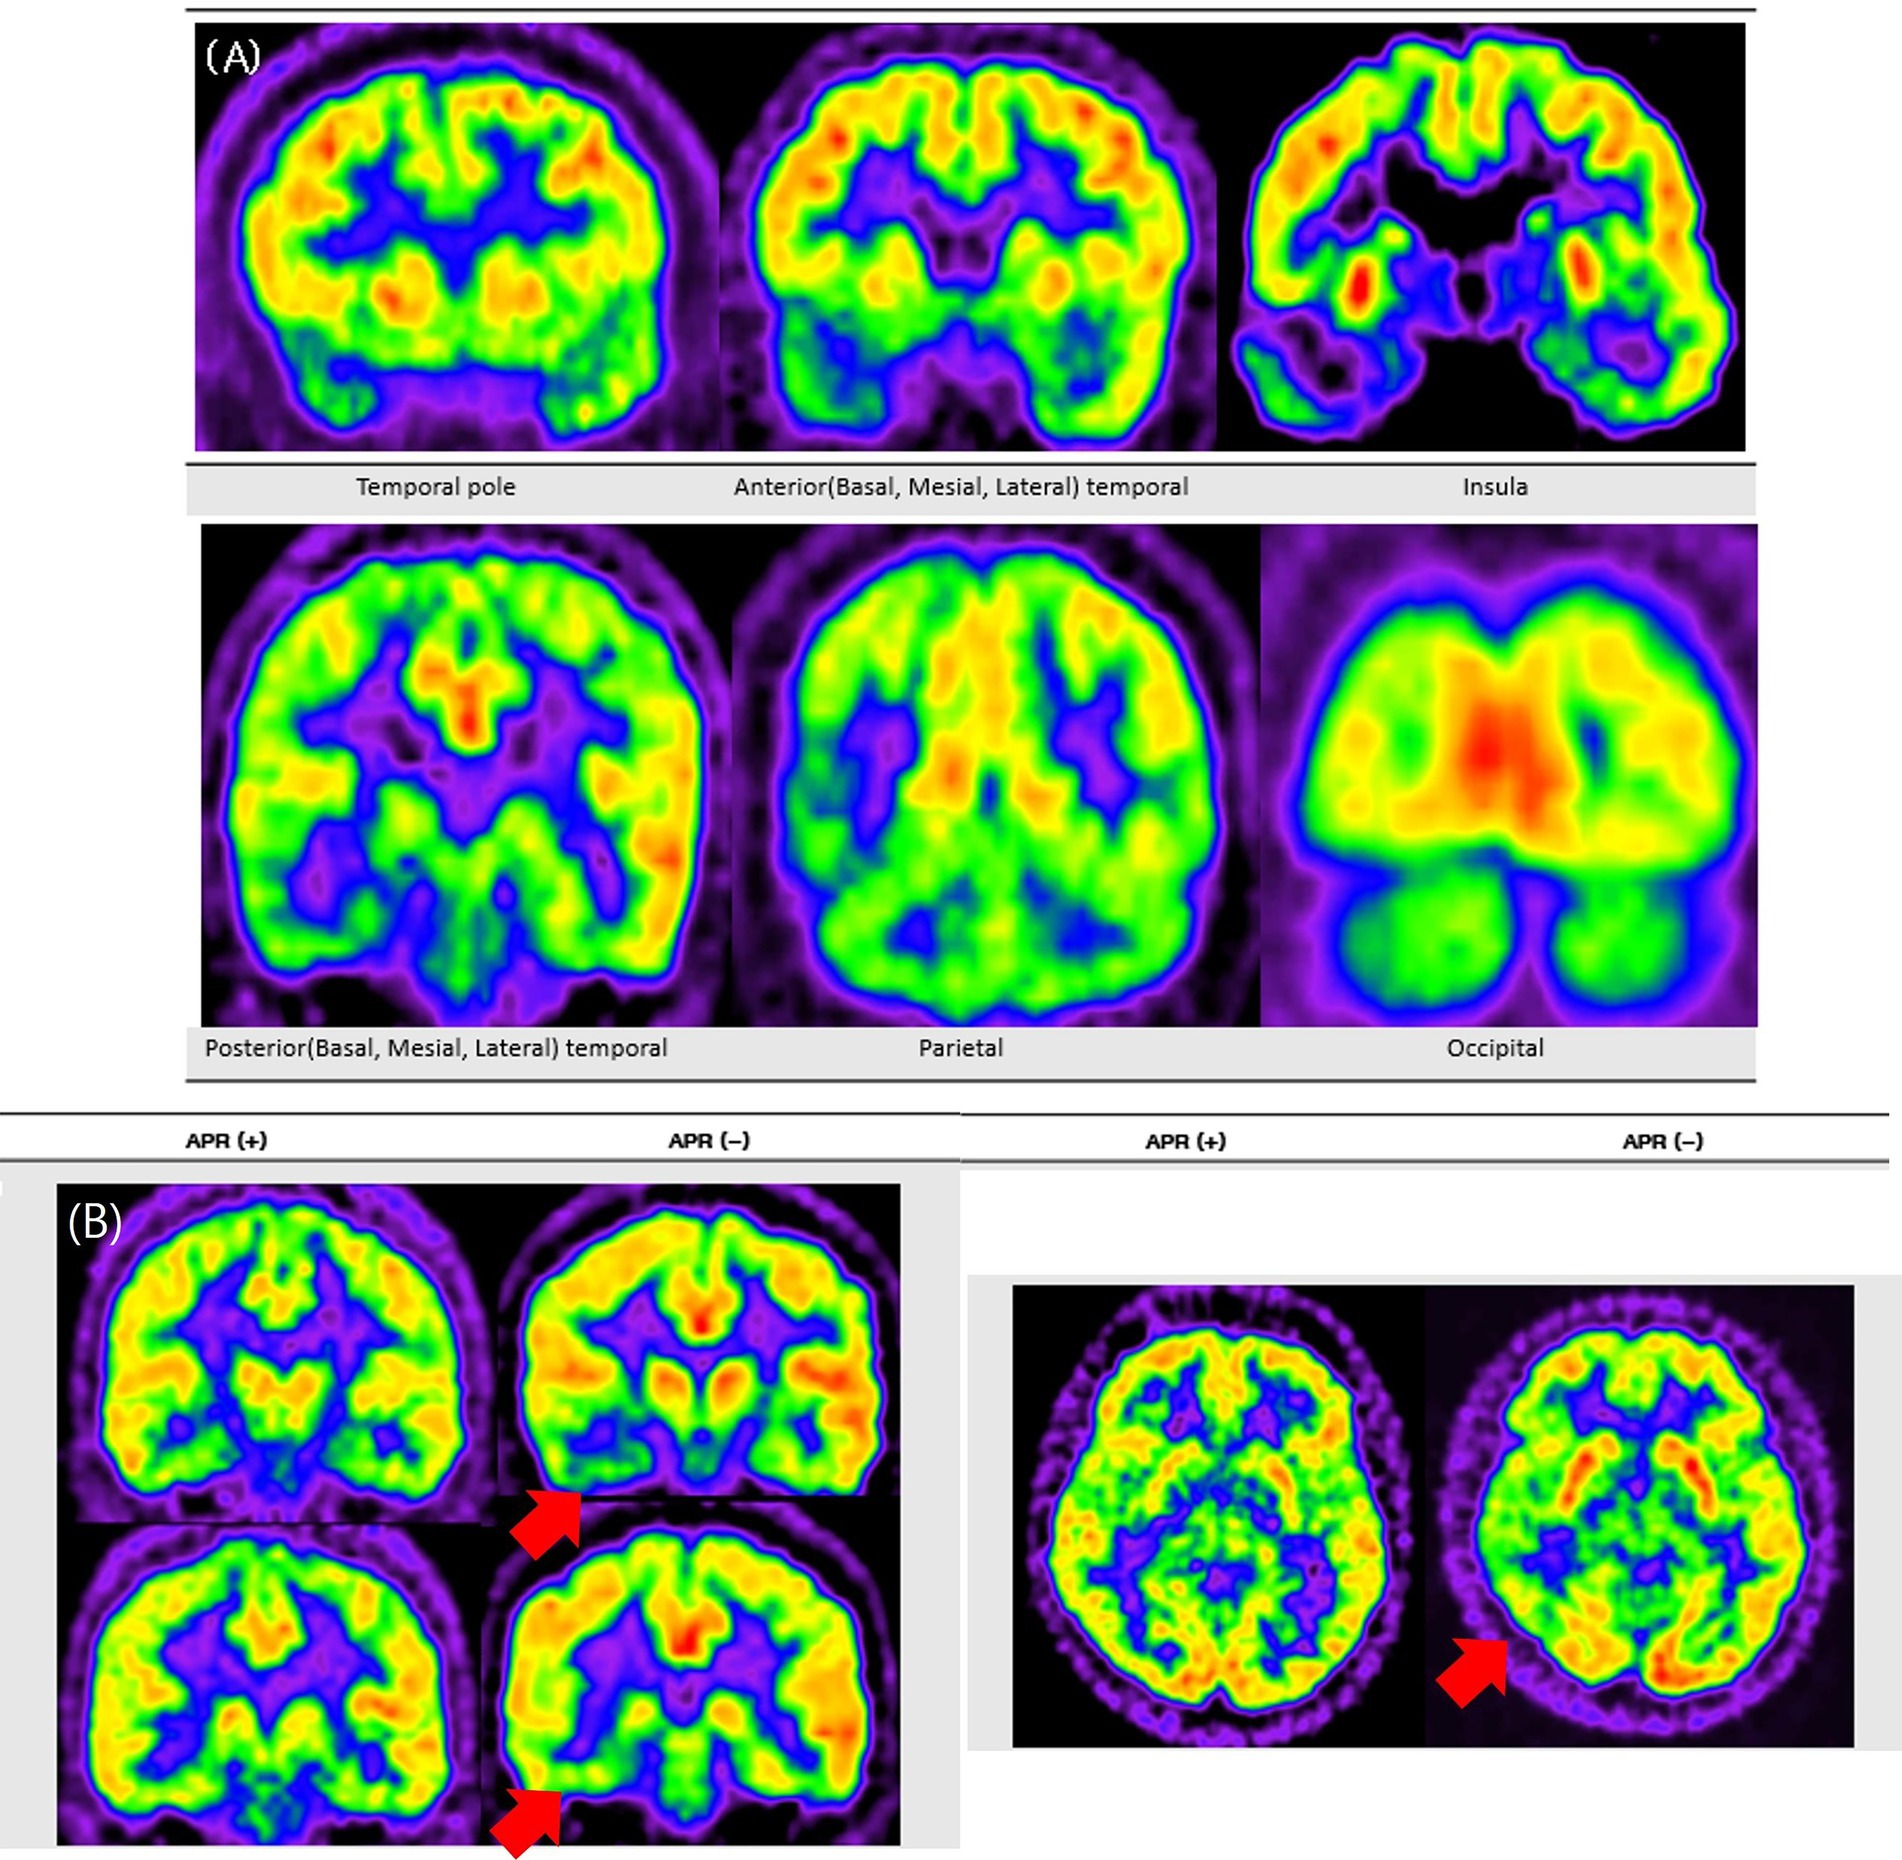

For a more standardized visual grading process, a reference image set was developed to illustrate each severity grade, ranging from absent or minimal (Grade 0) to moderate (Grade 1) and severe (Grade 2) hypometabolism (Figure 2). The reference images were used as a standard template to ensure consistency and reliability in hypometabolism severity ratings across all anatomical regions.

Figure 2

Visual grading examples of temporal hypometabolism on FDG-PET. This figure shows representative coronal FDG-PET images illustrating the three-grade visual scale used to classify the severity of temporal hypometabolism. Panel A represents normal symmetric metabolism with no reduction (Grade 0). Panel B shows mild localized reduction in metabolic activity (Grade 1), while panel C shows marked and extended reduction with clearly decreased FDG uptake (Grade 2). The figure demonstrates how visual grading was applied to categorize hypometabolism severity in this study.

Figure 2 illustrates the standardized three-point visual grading scale used in this analysis, whereas Figure 3 presents representative FDG-PET images contrasting APR + and APR − patients. These representative images clearly demonstrate more pronounced hypometabolism in posterior temporal regions of APR- patients, while other areas showed comparable metabolic activity between groups. This distinctive topographic pattern of metabolic alterations substantiates the specific association between posterior temporal hypometabolism, particularly in the lateral region, and impaired responsiveness during seizures in right MTLE patients.

Representative FDG-PET images contrasting APR− and APR+ patients. This figure presents FDG-PET images comparing patients with and without preserved ictal responsiveness (APR+ and APR−). Panel A shows a typical pattern of extensive hypometabolism in a representative patient with right mesial temporal lobe epilepsy, involving the temporal pole and extending to temporal, parietal, insular, and occipital regions. Panel B shows two patient examples, where red arrows indicate more pronounced ipsilateral posterior temporal hypometabolism in the APR− patient compared to the APR+ patient.